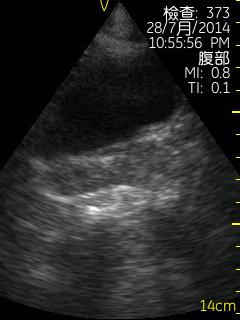

Vscan临床图片 腹部